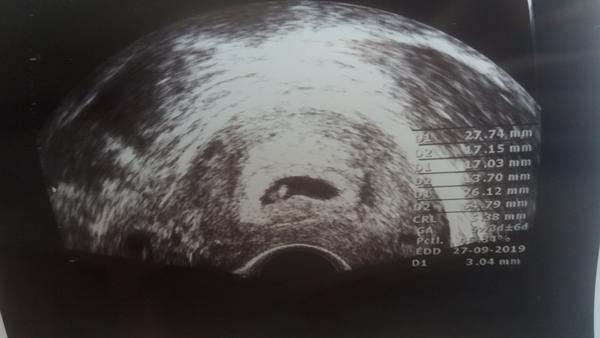

Holky, zítra jdu na první kontrolu, tak mi prosím držte palce, ať je vše v pořádku a miminko je v děloze, nejlépe i kdyby už bylo srdíčko. Zítra Vám napíšu 🙂